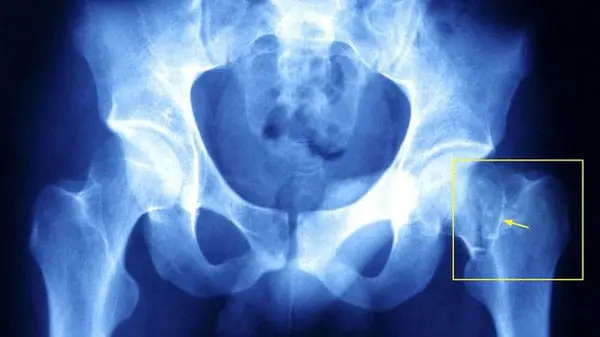

یک متخصص ارتوپدی با بیان اینکه کمبود ویتامینD از علتهای شکستگی و پوکی استخوان است، گفت: یکی از دلایل عمده ناتوانی عضلات در افراد مسن سطح پایین ویتامین D است.

نژادی اظهار کرد: پایین بودن سطح ویتامین D در اطفال باعث بیماری نرمی استخوان می شود و کمبود همین ویتامین در بزرگسالان باعث استئوپروز یا پوکی استخوان خواهد شد.

این جراح زانو در خصوص آمار ویتامین D در ایران، گفت: در تحقیقاتی که در ایران صورت گرفته است، از هر ۱۰۰ بیمار مبتلا به شکستگی استخوان ۹۰ نفر کمبود ویتامین D داشته و در تحقیقات دیگری که در کشور صورت گرفته ٦٠ تا ٨٠ درصد افراد دچار کمبود ویتامین D بودند که استفاده از مکملها به عنوان غنی کننده مواد غذایی لازم است.